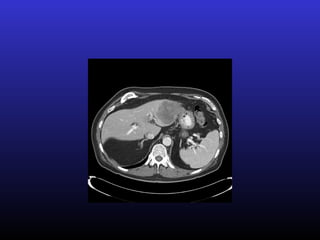

• #14 Vertebral met – localized somatic pain to vertebrae, visceral pain in abdomen – and neuropathic pain from nerve root involvement – ex – many cancer patients will have several sources and can have a combination of how they’re experiencing pain